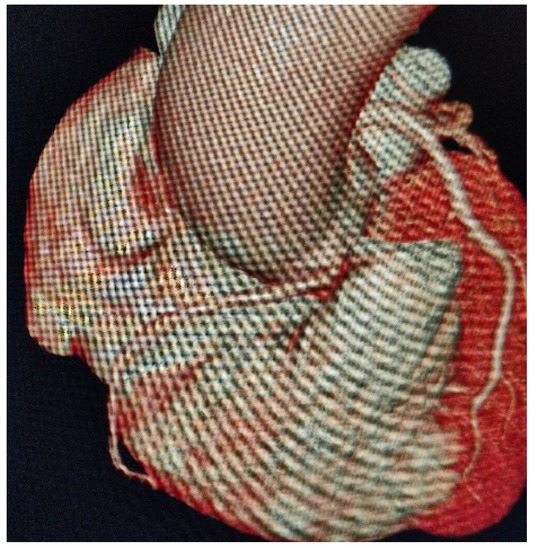

A Curve Maybe to Narrow: Description of an Anomalous Course of the Right Coronary Artery

Pastorini, G.; Bertone, E.; Talenti, A.; Feola, M. A Curve Maybe to Narrow: Description of an Anomalous Course of the Right Coronary Artery. Diseases 2021, 9, 62. https://doi.org/10.3390/diseases9030062